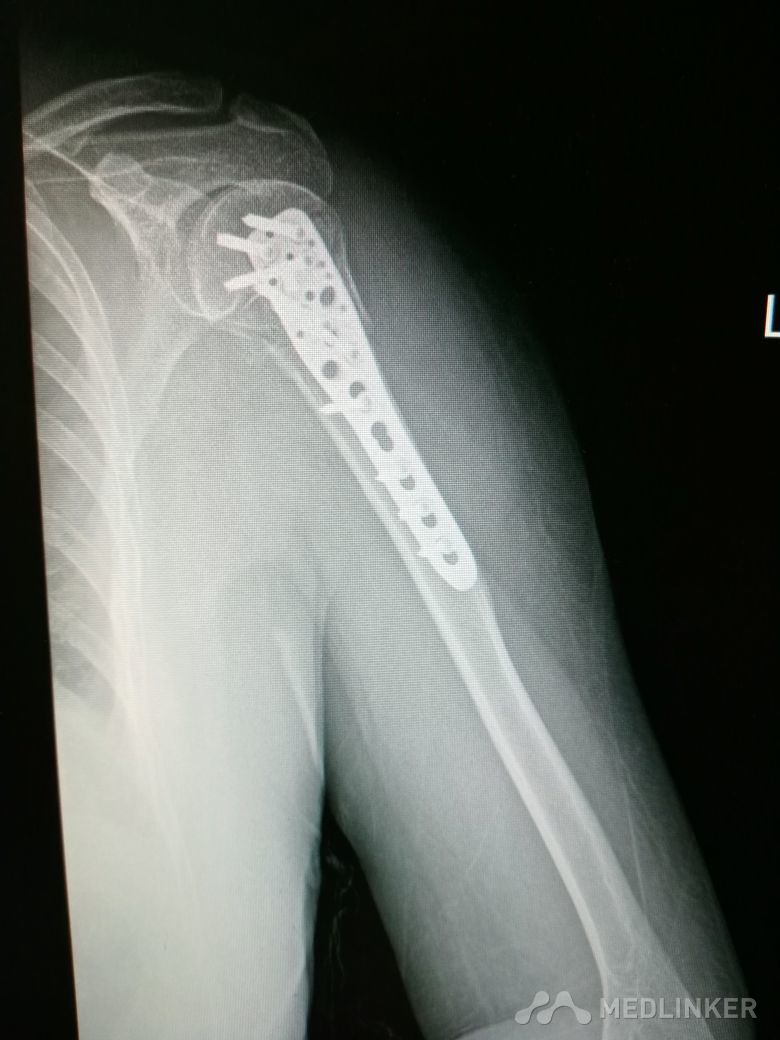

肱骨近端骨折 Neer IV型

患者,女性,55岁,因外伤致左肩疼痛六小时入院,既往无其他慢性病史

查体 右肩肿胀,畸形,活动受限,压痛,皮下淤血,右桡动脉搏动存在

完善相关检查,在腰麻下行右肱骨近端骨折切开复位内固定术

肱骨近端骨折占到肱骨骨折的45%,肱骨近端锁定钢板具有低切迹、高弹性、生物力学性能优良等特点,可以起到角度稳定控制旋转的作用。但是对于严重粉碎性肱骨近端骨折而言,单纯的肱骨近端锁定钢板不一定能够提供稳定的固定,手术之后仍有可能出现内翻塌陷、前后成角、螺钉切出、骨折畸形愈合、骨折不愈合等并发症。